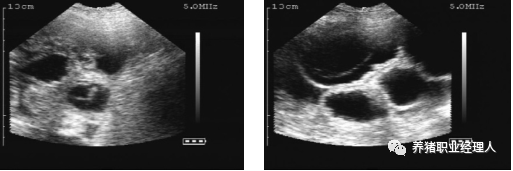

有囊肿的空怀母猪。这头母猪永远不会怀孕。

有一个副卵巢囊肿的母猪。这头母猪能够怀孕。

扫描配种第24天的母猪,大的胚胎囊可以很容易的看到。